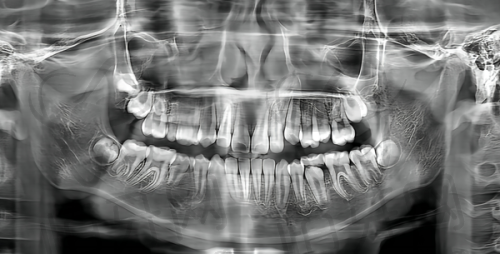

北京劲松口腔医院的种植团队都接受过国内外精尖培训,掌握即刻种植、上颌窦提升等高端技术。医院还配备了CBCT等精良设备,确保种植手术精细安心。特别多缺牙患者都说在这里种牙"跟买菜一样简单",完全不用担心!

想预约北京劲松口腔医院的骨干医生?联系方式特别简单:可以拨打医院电话138***7642询问。医院位于方庄地区,拥有3500㎡的超大空间,30台牙椅,设备超级齐全。从CBCT到激光治疗仪应有尽有,确保诊疗精细效率高。